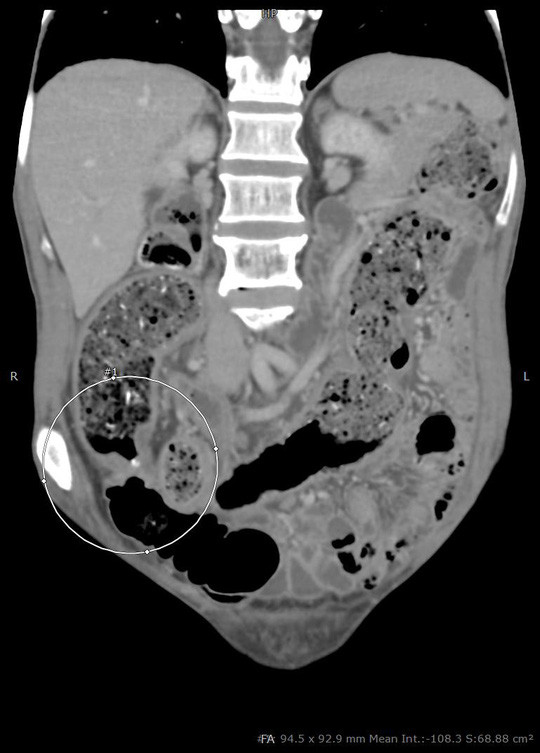

| Vị trí u gây tắc ruột suýt vỡ của người đàn ông |